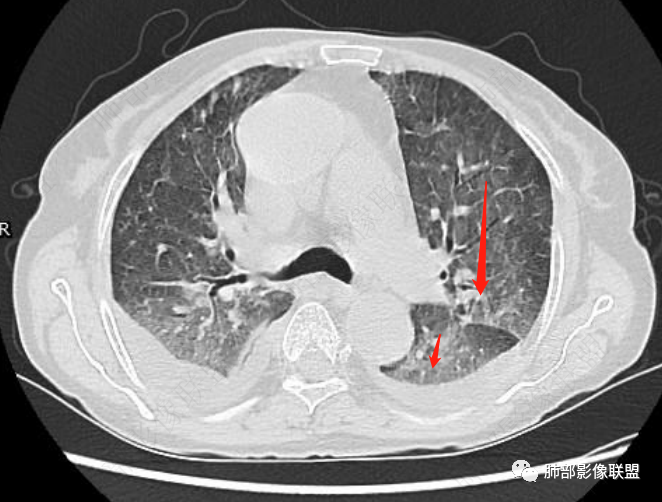

片状磨玻璃影,多发结节,类风湿肺炎?

发热,有类风湿性关节炎、糖尿病基础病,长期口服激素及免疫抑制剂,双肺多发磨玻璃影及小叶间隔增厚,蜂窝影,支气管扩张考虑非特异性间质性肺炎存在,左肺上叶不规则结节影,周围长毛刺局部肺气肿,考虑慢性炎症,结合pct及crp升高考虑细菌感染,另真菌g升高考虑结合宿主因素,真菌感染需要积极排除。

肺部影像联盟晨读病例有类风湿肺病史,影像蝶翼状磨玻璃影,伴散在结节、双侧胸水,考虑PJP。

免疫抑制状态,G试验明显升高,两肺弥漫性病变,首先考虑PJp,建议肺泡灌洗液NGS

考虑RA相关间质性肺病(RA—ILD),两肺磨玻璃影,长期使用激素,不除外合并PJP。

老年女性,外阴溃疡伴发热,有类风、糖尿病病史,血象及炎症指标高,G试验升高;影像:磨玻璃密度(中央分布为主)胸膜下蜂窝状改变心影增大、两侧胸腔少量积液;小叶间隔增厚,结节;考虑:1.中央分布为主的GGO需考虑:肺水肿、出血、PJP、肺泡蛋白沉着症;2.胸膜下间质性改变蜂窝肺,需考虑UIP、CTD-ILD,综合:两元论:CTD-ILD奴卡,或肺水肿

①影像表现复杂:较弥漫间质性改变,对称磨玻璃密度为主,小叶间隔增厚,有一定重力分布趋势,未见明显纤维化,气囊及蜂窝位于肺边缘,未见典型“月弓征”。心脏影增大,双侧胸腔积液。

这即可见于间质性肺病,也可见于真菌感染(如PJP)、病毒感染,类风湿,以及肺水肿等等。

一般而言,如存在磨玻璃密度影浑浊,有重力分布趋势,肺表面蜂窝影,胸腔积液等等,并不常见于单纯PJP,除非其他因素叠加。

上肺斑片影、结节影,夹杂纤维条索影,边界清楚,新旧不等,胸膜牵拉明显等等,符合较典型继发性肺结核表现,但它却未必是此次就医主要责任病原体!